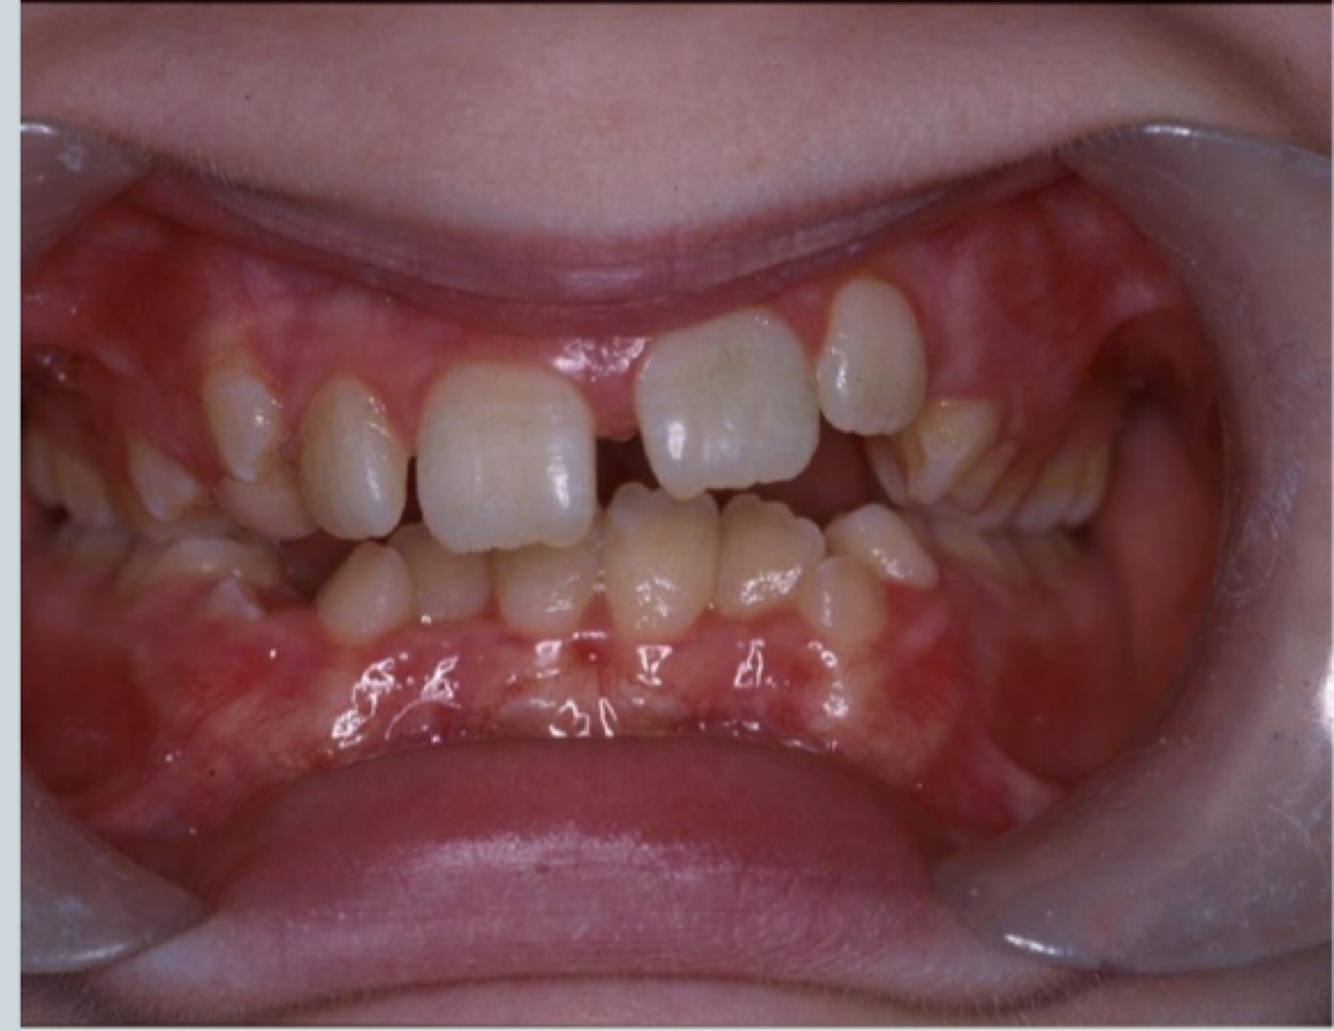

What can you see - features of CLASS II

Well aligned arches

Some teeth need to come through

Classical increase in overjet - cheek retractors show extent of the overjet